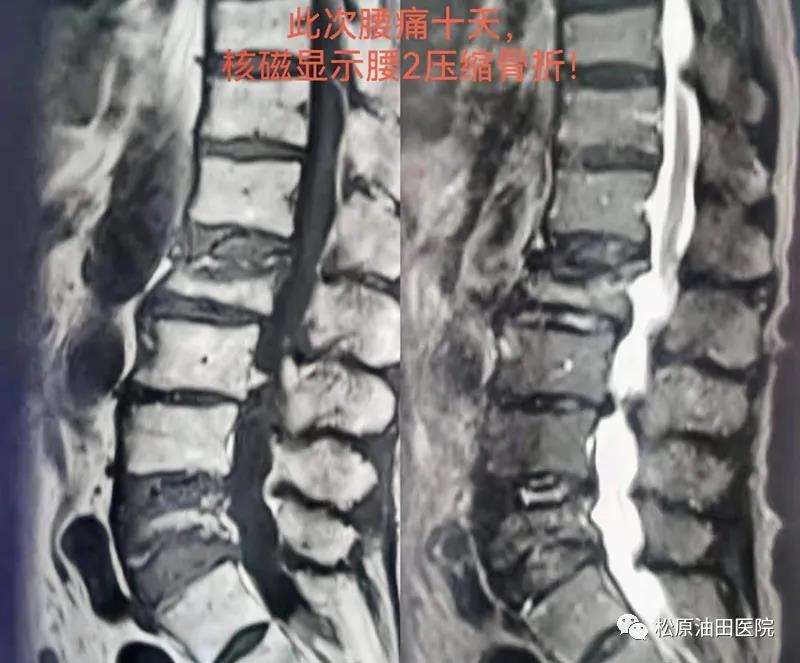

据了解,骨一科已经开展椎体成形术(PVP)十余年,一直以来,手术都是在C臂透视引导下进行的,经过多年的研究和探索,手术时间已经可以控制在半小时左右,其中穿刺手术时间约15至20分钟,等待骨水泥硬化时间约12分钟。油田医院今年引进了G臂X光机后,大大缩短了穿刺手术时间。23日手术的这位79岁女性患者,有2个月前腰5压缩骨折病史,腰椎X光片及核磁显示:腰5变扁,椎体内有异常信号。患者新发腰痛,考虑其他椎体骨折可能,复查腰椎核磁,结果显示腰2椎体压缩骨折,经全科讨论后,明确临床诊断为腰2椎体压缩性骨折和重度骨质疏松症,治疗首选椎体成形术,于是这位患者成为骨一科第一例G臂引导下PVP手术病人。

患者术后腰痛症状明显减轻,术后2小时离床活动,无不良反应,术后腰椎X光片显示:骨水泥弥散满意,腰2椎体高度恢复良好。